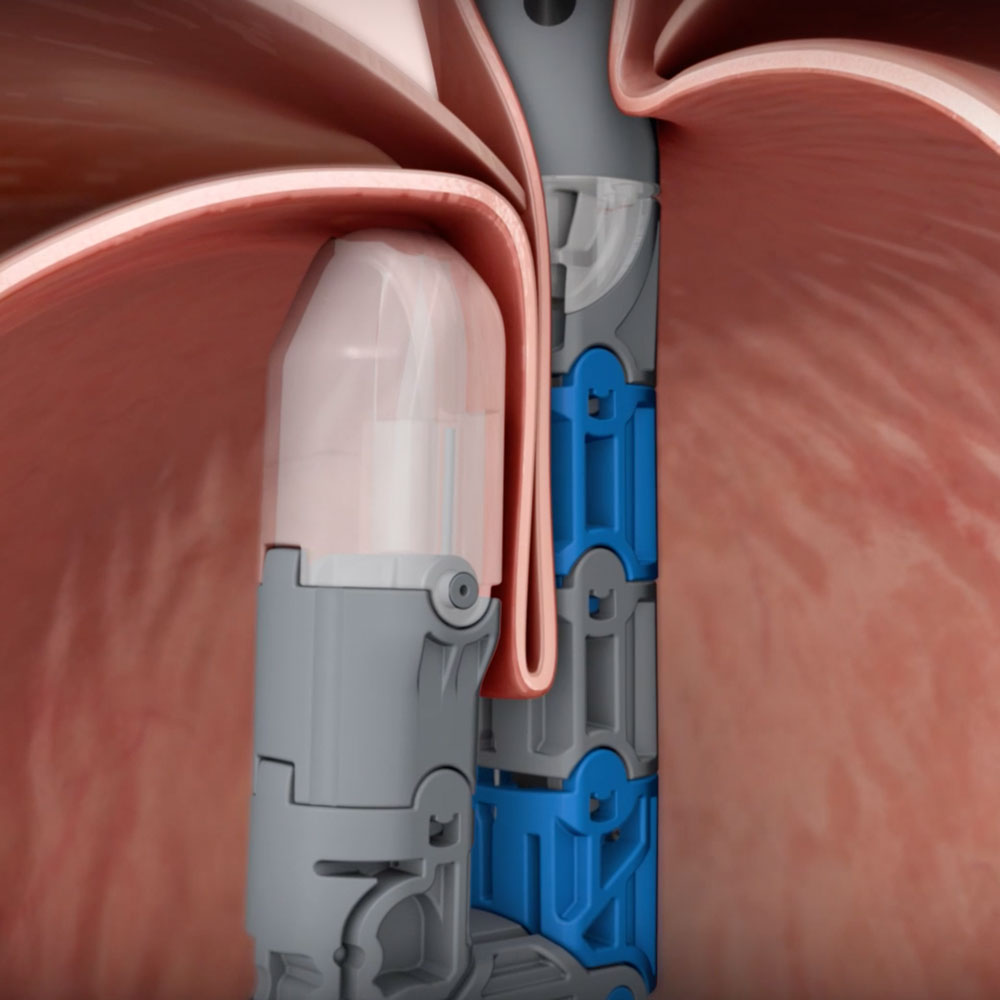

Step 2: The Gastroenterologist – Uses the TIF technique to rebuild the anti-reflux valve through the mouth.

The TIF procedure reconstructs the esophageal valve that keeps stomach acid from entering the esophagus. TIF restores the body’s natural protection against reflux without incisions and is performed directly after hiatal hernia repair, under the same general anesthesia. The result is relief from acid reflux, heartburn, and all the effects associated with GERD. Dr. Barnes and Dr. Kandiah utilize their individual areas of expertise to complete the cTIF procedure and give patients a new chance at life without acid reflux.